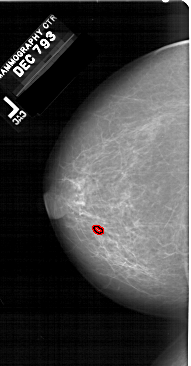

A_1513_1.LEFT_MLO

LEFT_MLO LINES 6496 PIXELS_PER_LINE 3496 BITS_PER_PIXEL 12 RESOLUTION 43.5 OVERLAY

FILE: A_1513_1.LEFT_MLO.OVERLAY

TOTAL_ABNORMALITIES 1

ABNORMALITY 1

LESION_TYPE CALCIFICATION TYPE PLEOMORPHIC DISTRIBUTION CLUSTERED

ASSESSMENT 4

SUBTLETY 1

PATHOLOGY BENIGN

TOTAL_OUTLINES 1